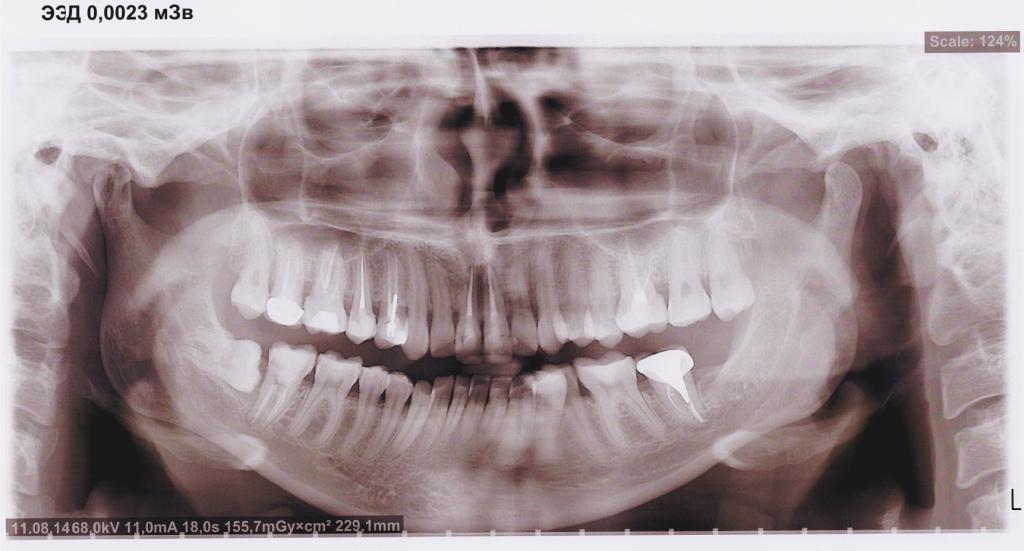

Была с этим снимком у хирурга. Врач сказала, что нужно лечить тридцать седьмой зуб, но что с ним не так не сказала. Сказала, что все расскажет терапевт, но к терапевту пока идти не могу, а вопрос с тридцать седьмым зубом меня мучает, т.к. там коронка, и ее видимо придется снимать, и меня это пугает.

Что с зубом? И как происходит снятие коронки?

На верхушке корня тридцать седьмого зуба имеется обширное воспаление. Для его лечения необходимо извлечь вкладку и коронку. По окончании лечения снова изготовить данную конструкцию.